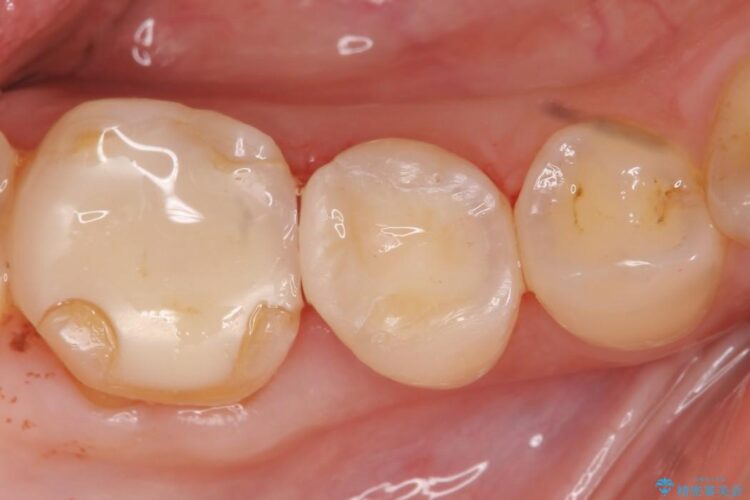

ぱっと見ただけでは特に問題ないように見えますが、レントゲンをよく確認すると詰め物と歯の間に隙間がはっきりと確認ができます。

適合不良であるインレーを放置するリスクを患者様へ説明してご納得いただいた上で、オールセラミックインレーで治療を行うこととしました。